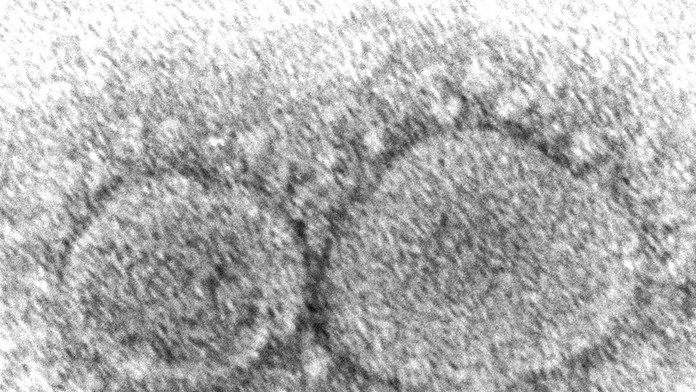

Archívna snímka z elektrónového mikroskopu z roku 2020, ktorú sprístupnilo Centrum pre kontrolu a prevenciu chorôb (CDC), zobrazuje nový koronavírus SARS-CoV-2. Zdroj: TASR/Hannah A. Bullock, Azaibi Tamin/CDC via AP